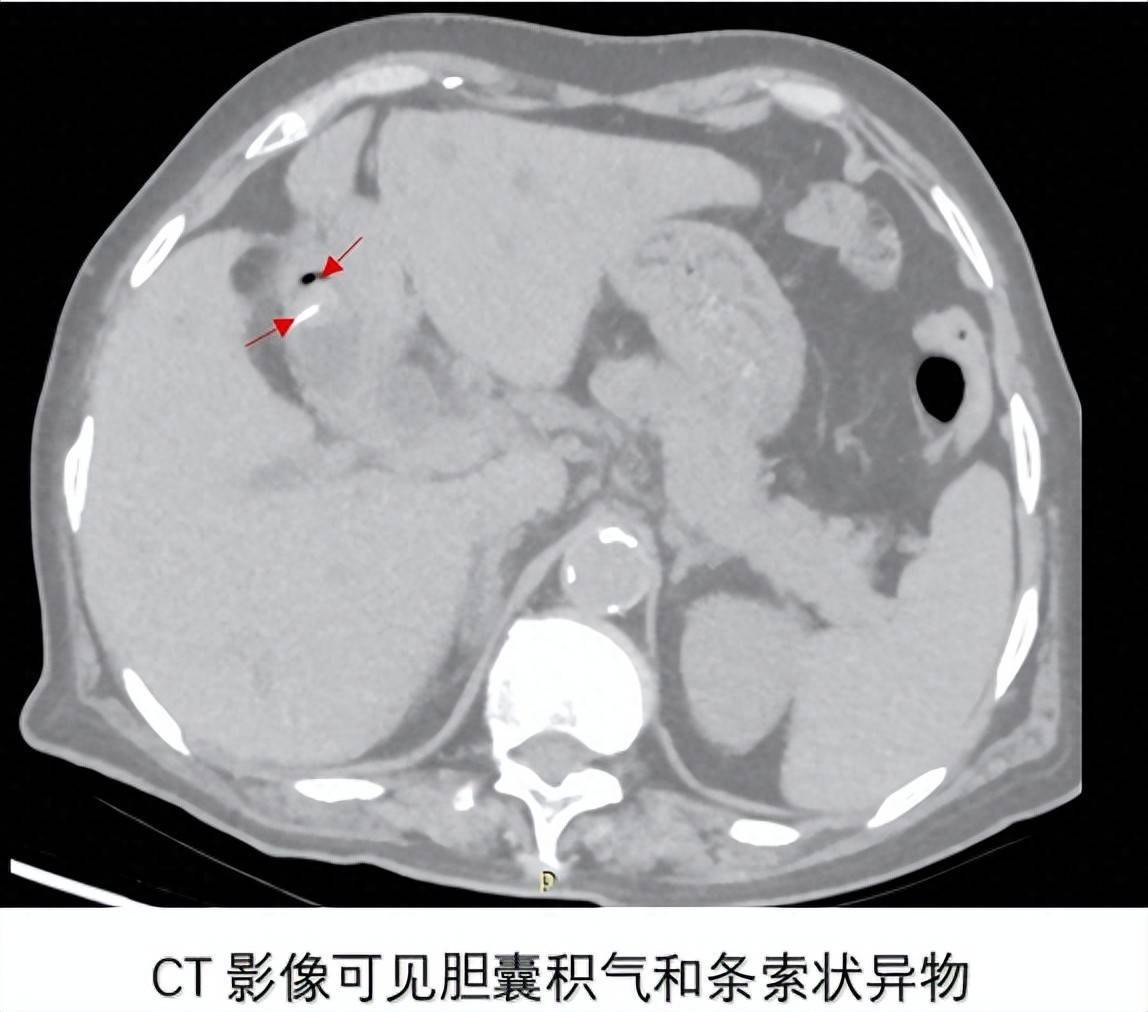

患者为79岁女性,因“间断上腹痛10月余,加重伴皮肤巩膜黄染、寒战发热3天”入院。既往有高血压病史5年,无手术史。入院后CT检查提示:胆囊结石、胆囊积气,胆囊内可见条索状高密度影,胆囊与胃毗邻,肝内外胆管扩张、胆总管下段结石。这种影像学表现高度提示可能存在胆囊胃瘘——一种临床上极为罕见的并发症。

面对罕见病例,开滦总医院肝胆外科二病区与CT室等相关专家立即展开深入讨论。结合患者CT显示的胆囊内金属密度影、胆囊积气以及胆囊与胃紧密连接的特征,专家团队高度怀疑存在胆囊胃瘘,同时合并胆囊结石、胆总管结石。经过充分论证,决定为患者实施腹腔镜探查+胆囊切除+胆总管切开取石+T管引流术,并做好术中处理瘘口的准备。